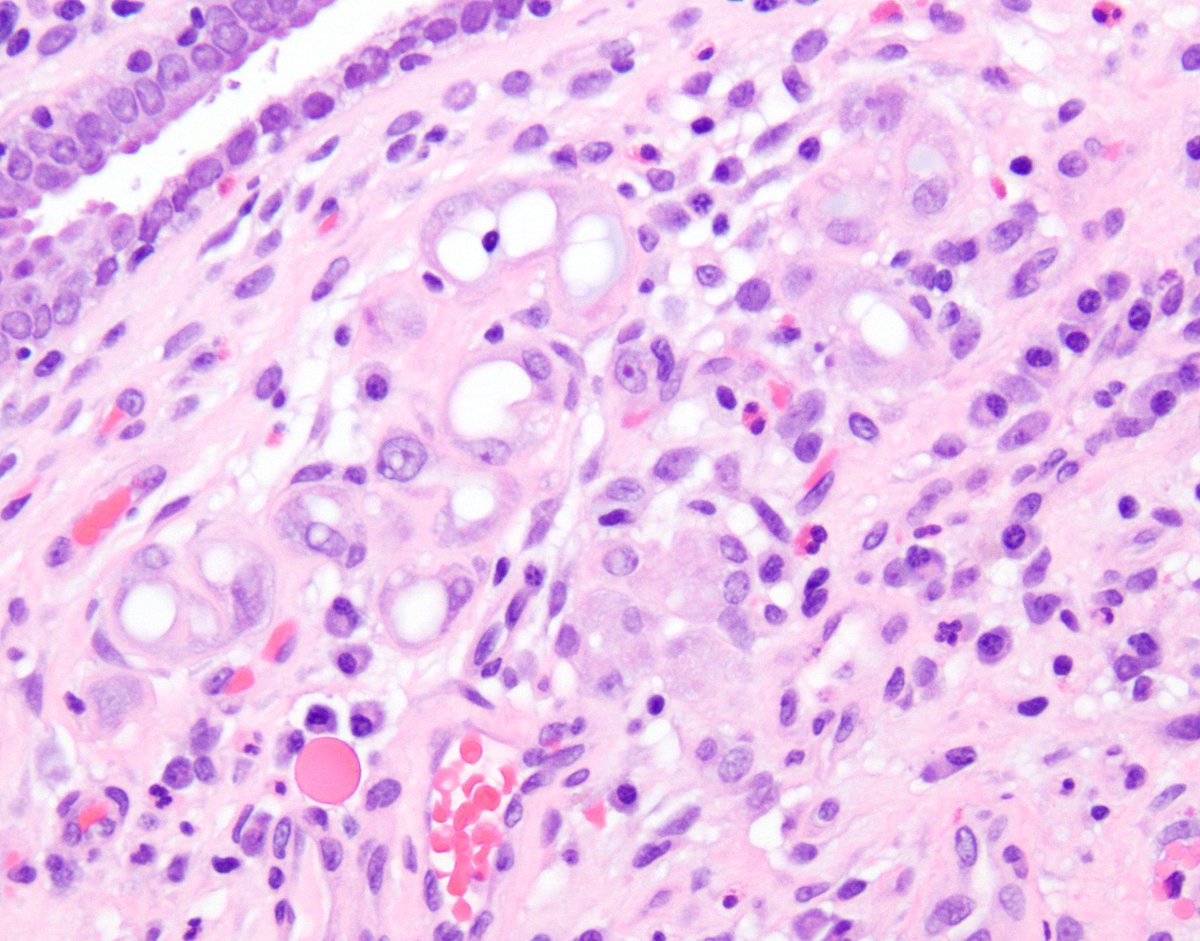

Lipid-rich urothelial carcinoma ✔️frequently associated with conventional urothelial carcinoma ✔️ lipid nature of the vacuolar content has been confirmed by EM ✔️ poor prognosis ✔️ + CK7, CK20 (photo), 34betaE12 #gupath #pathology #uropathology